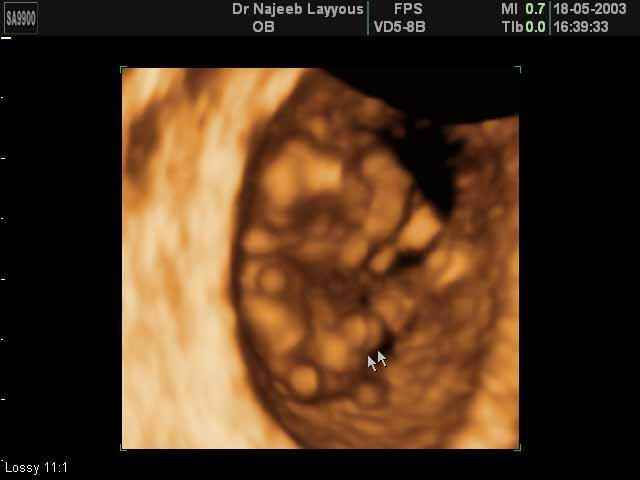

- First Trimester Ultrasound Photos

3D First Trimester Ultrasound Scan Photos ( Early Pregnancy Ultrasound Photos ) | Dr N Layyous